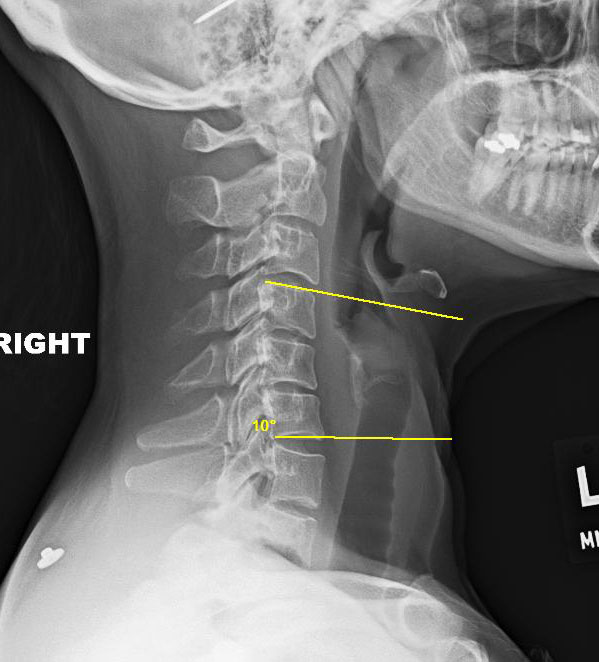

Измерение кифоза грудного отдела: Рентгеновские снимки